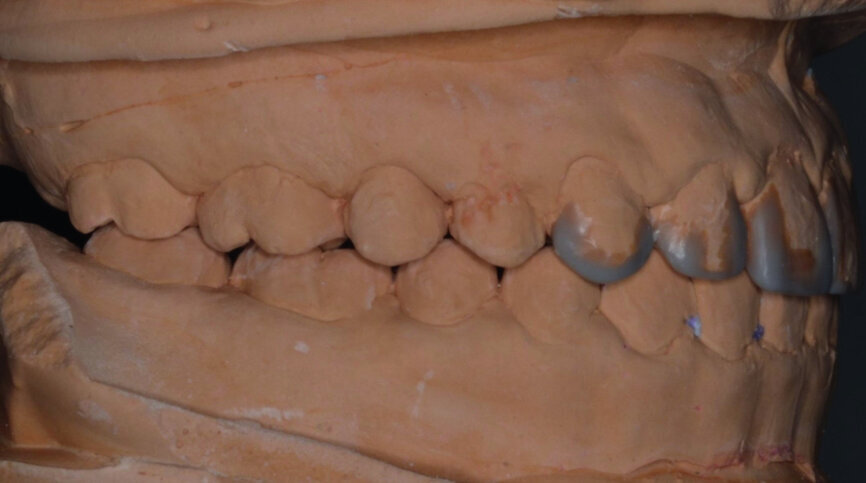

Then occlusal analysis (Figs. 11–21) was performed:

- Initial CR mounting (Figs. 19–21).